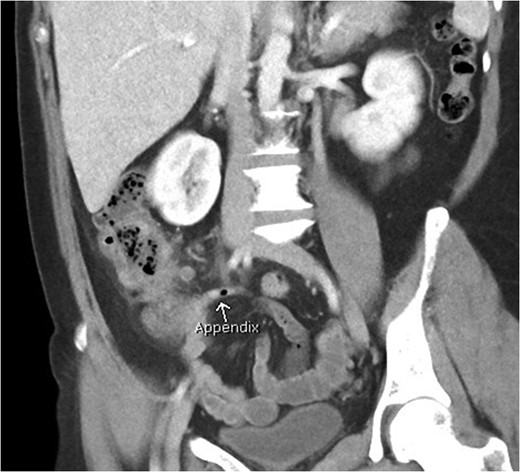

Coronal view of patient with appendicitis. Dilated and thick walled appendix (arrow).

Axial view of patient with appendicitis. Eccentric caecal wall thickening (maximal surrounding the appendiceal orifice) with layered mural contrast enhancement secondary to prominent submucosal oedema (arrow) and prominent pericolic fat stranding represent the CT manifestation of the surgical phlegmon.

Appendicitis features include a fluid-filled dilation (>6 mm) and thickening of the appendiceal wall with mild-to-moderate peri-appendiceal fat stranding [5]. Peri-caecal inflammation may occur, characterised by segmental eccentric bowel wall thickening centred over the appendiceal orifice. Importantly, the submucosa (expanded and low density), muscularis and serosa (both slightly thickened and enhancing more than normal) may be delineated in a stratified or layered pattern. Other complications may be present such as perforation or abscess formation, which are seen as rim enhancing collections. Rarely, hepatic abscesses may be present as a manifestation of portal pyaemia, characterised by diffuse liver lesions close to the portal vein tributaries.